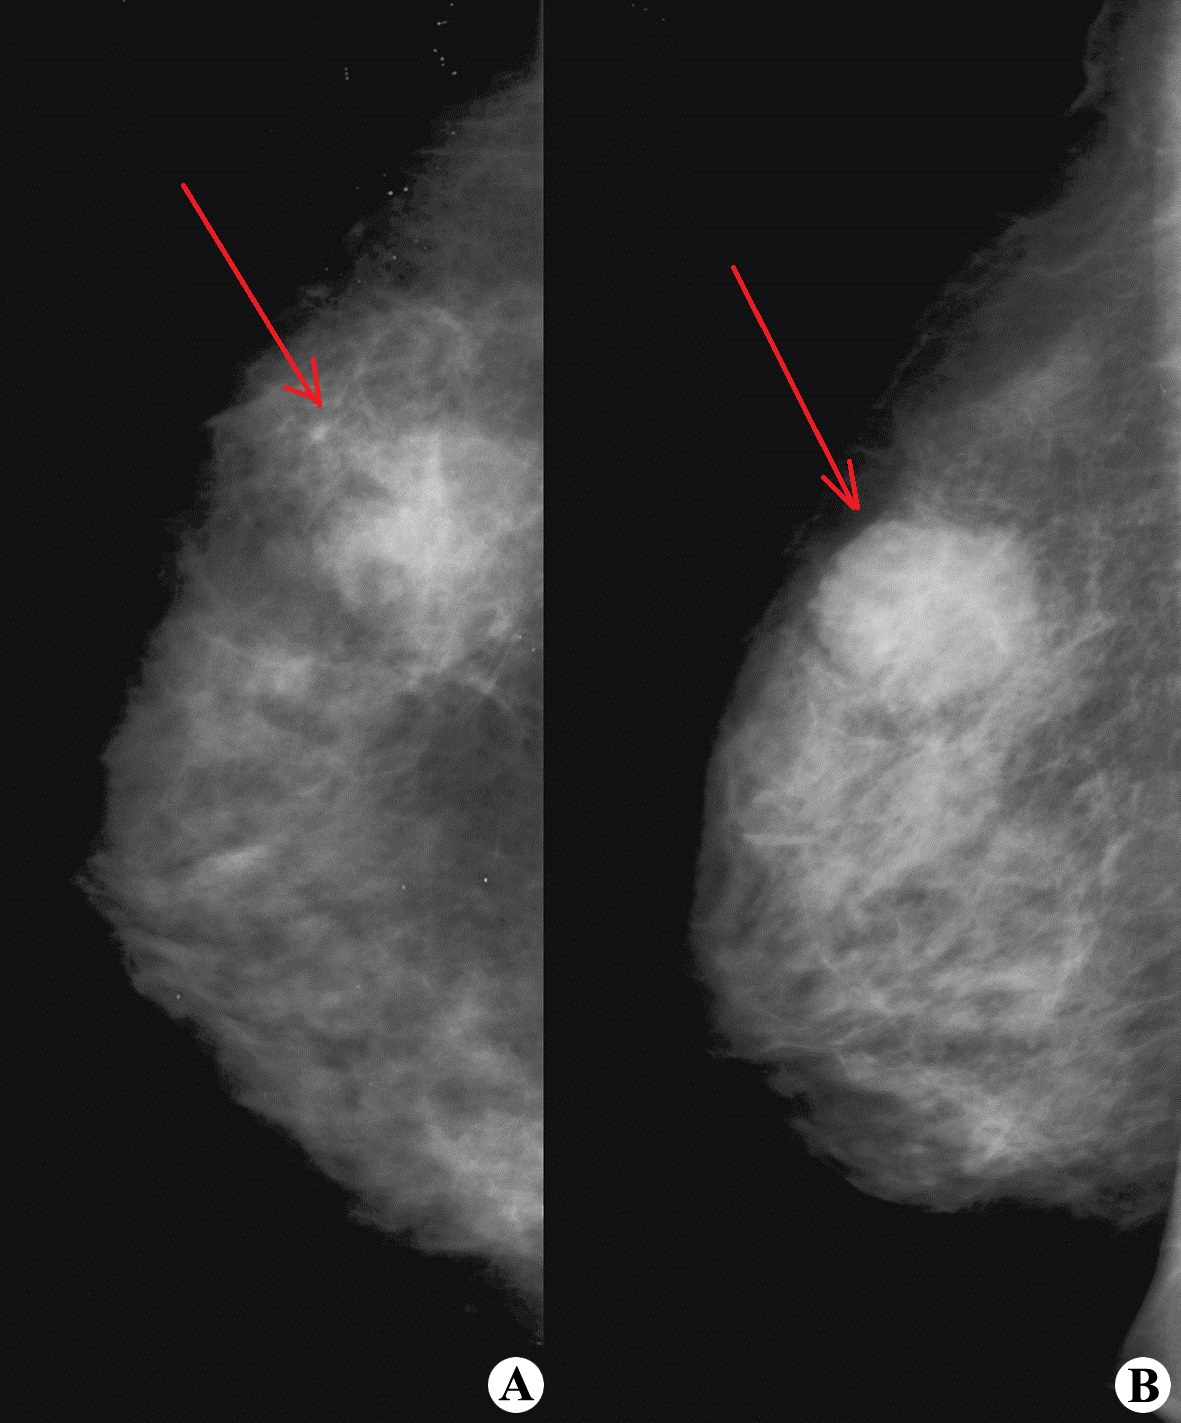

乳腺钼靶X线检查发现乳腺癌

然后,医生会利用乳腺彩超、专用钼靶X线或MRI等影像学检查来获取进一步的诊断信息,部分患者还会结合穿刺活检、乳腺导管造影等,以利于制定个性化的治疗方案。

乳腺癌的发病率与年龄有关,25岁后逐渐上升,45~54岁组达到高峰,55岁以后逐渐下降。因此,美国癌症协会曾建议:35~39岁的女性应进行一次乳腺钼靶X线检查,40岁以后每两年复查一次,50岁以后每年复查一次。

超声发现乳腺浸润癌